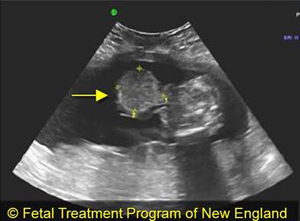

Omphalocele

Omphalocele is a condition in which loops of intestines (and sometimes parts of the stomach, liver and other organs) protrude from the fetus’s body through a hole in the abdominal wall. The hole is located at the belly button and is covered by a membrane, which provides some protection for the exteriorized organs. The umbilical cord inserts at the top of this membrane rather than on the abdomen itself. Omphalocele is often confused with gastroschisis, a similar condition in which the hole in the abdominal wall is located to the side (usually the left) of the umbilical cord.

Omphalocele can be detected through ultrasound from 14 weeks of gestation; however, it is easier to diagnose as the pregnancy progresses and organs can be seen outside the abdomen protruding into the amniotic cavity. Because of the high risk of associated conditions, a prenatal test called an amniocentesis may be performed to help detect chromosomal and heart anomalies.